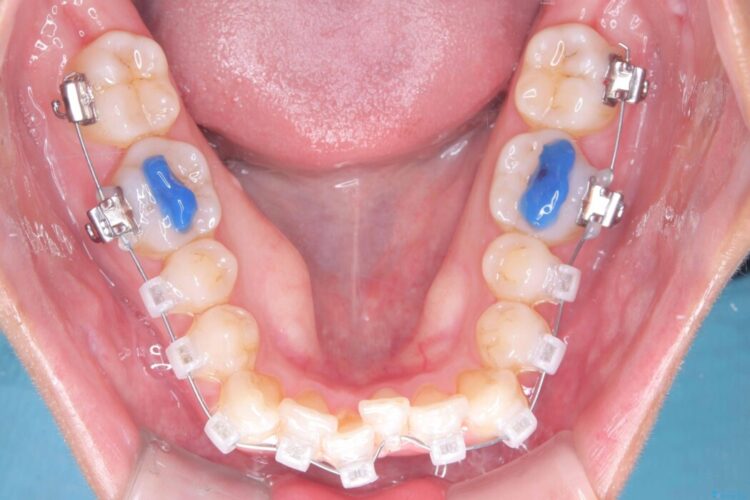

矯正検査の結果、非抜歯にてワイヤー矯正を行うこととしました。

ガタつきのほかに反対咬合も認められたため、見た目だけでなく嚙み合わせも同時に改善していきます。